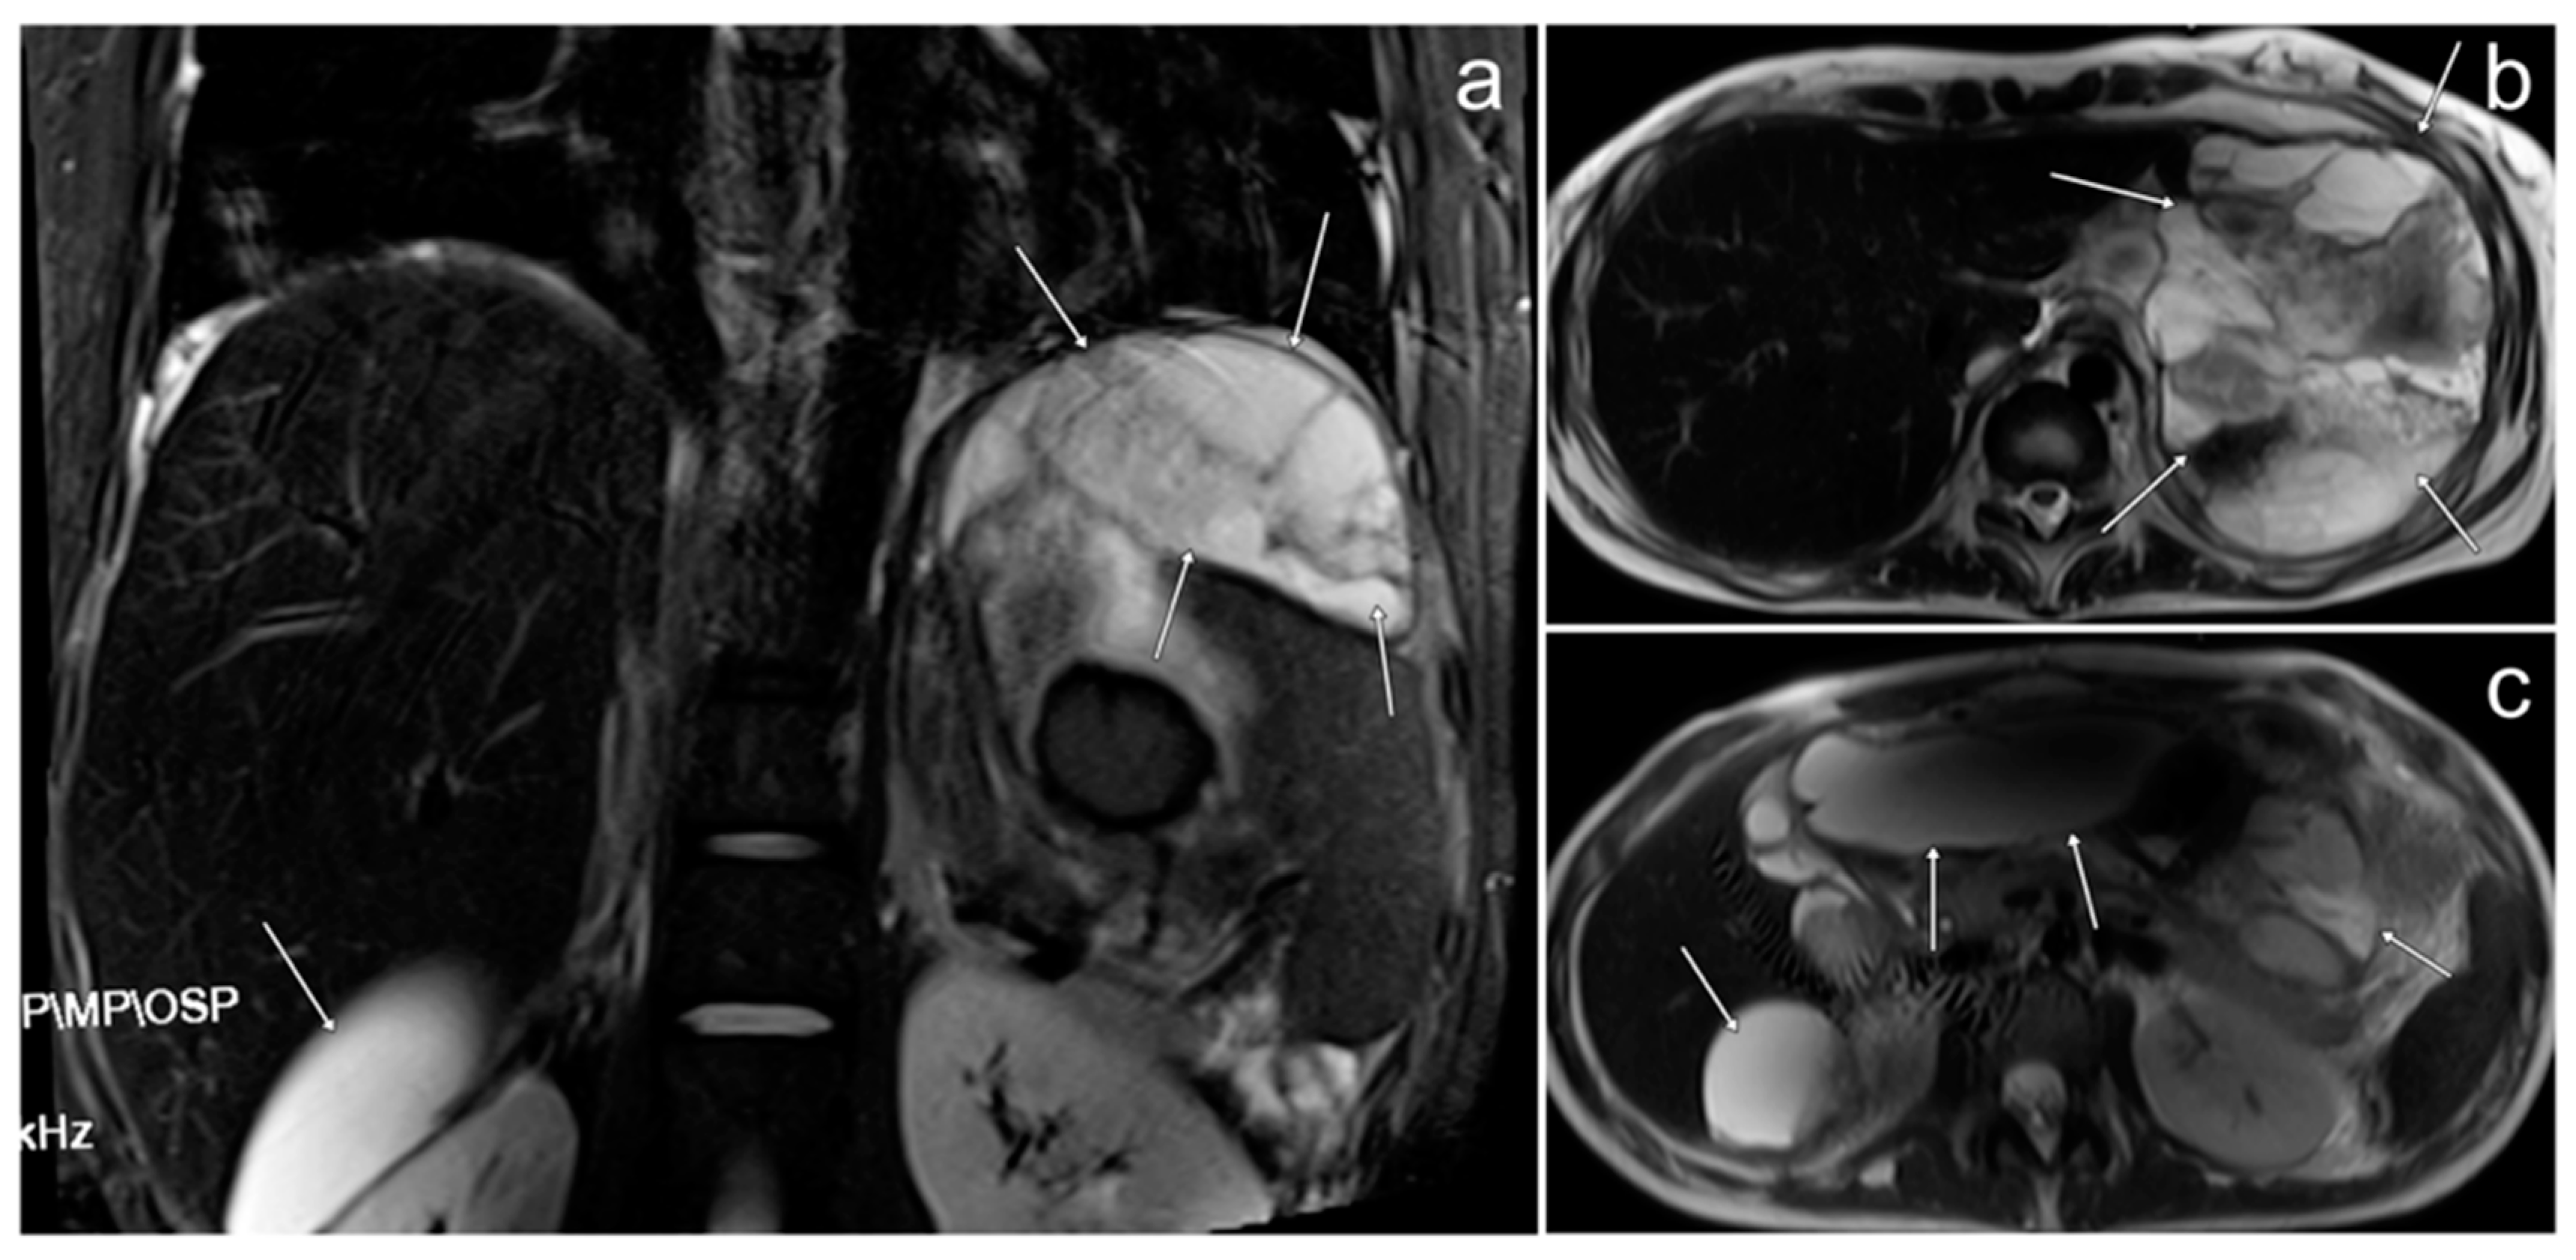

3.8. Pelvic Plexiform Neurofibroma

3.8.1. Case 1

3.8.2. Case 2

3.8.3. Case 3

| Plexiform neurofibroma | extensive, infiltrative mass spreading along nerve plexuses; high signal on T2WI; “target sign”; “reverse target sign”; no diffusion restriction | - | usually asymptomatic; associated with neurofibromatosis type 1 |